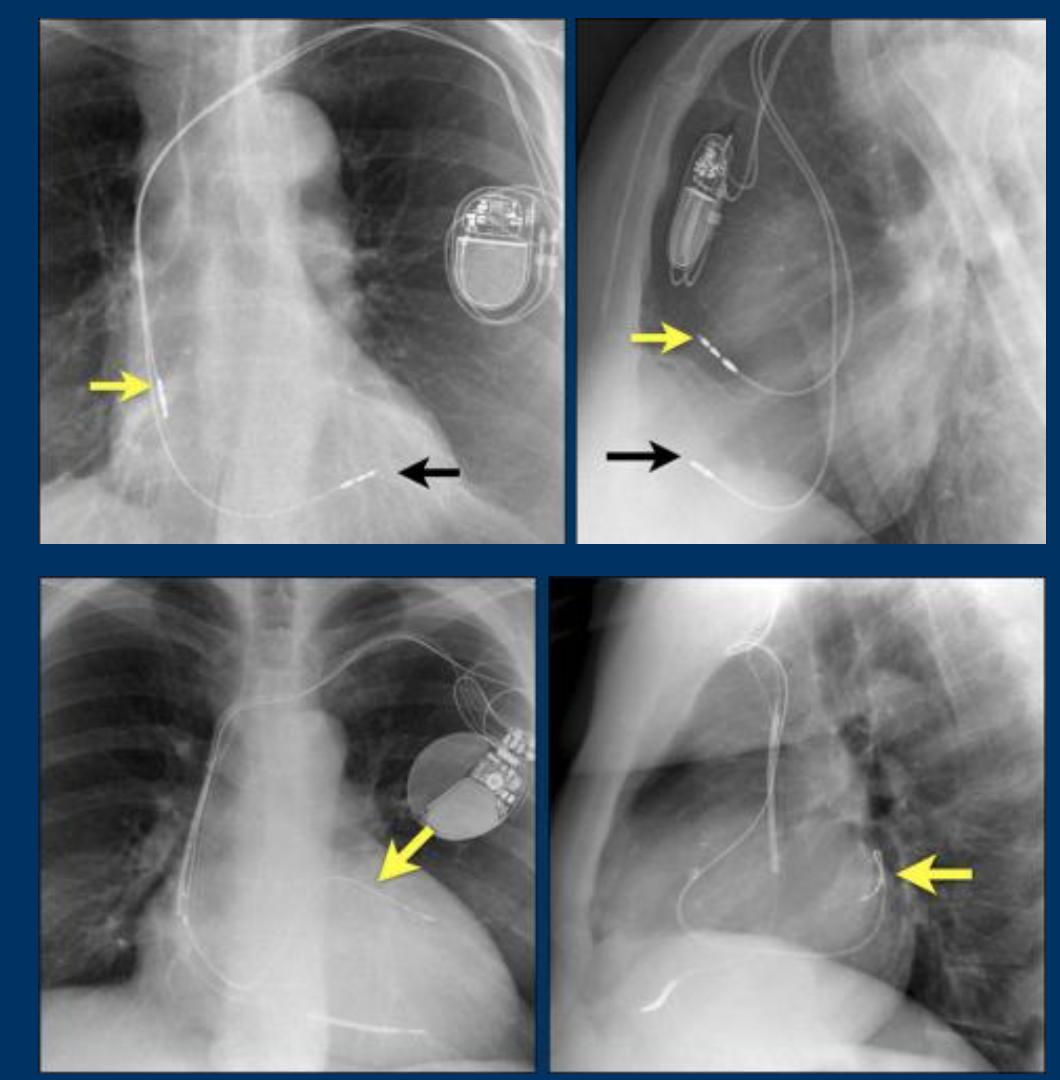

What devices are imaged?

Where are the leads placed?

1 PPM

2: Implantable cardioverter-defibrillator (ICD)